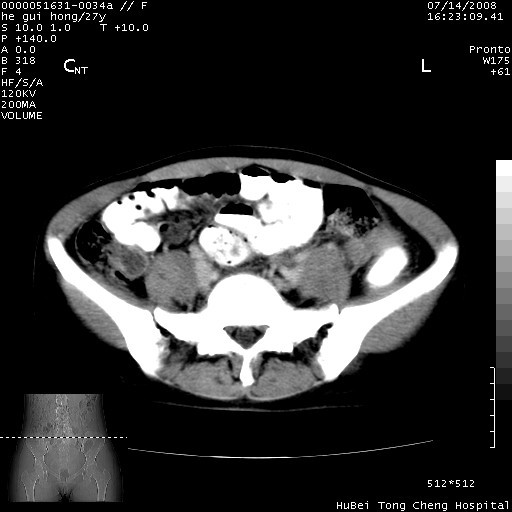

以下是引用杀毒软件在2008-7-20 8:03:00的发言:[br]支持双侧卵巢囊腺瘤可能性大!

以下是引用zjzjr在2008-7-20 13:36:00的发言:[br]双侧附件囊腺瘤可能性大!